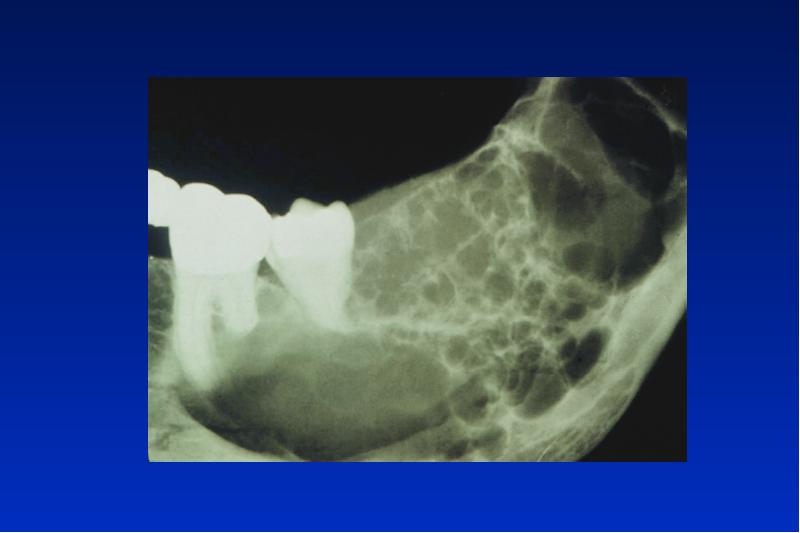

- 63. Myxom lokal invasiv wachsender ectomesenchymaler Tumor ohne Kapsel multilokuläre Osteolyse (Seifenblasen)